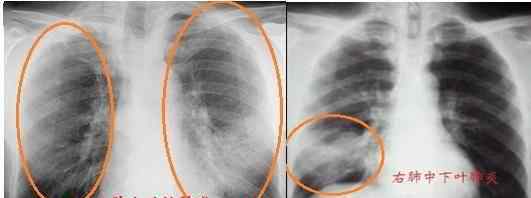

1.肺部炎症。这是胸部X线检查的主要目的。所有发烧、咳嗽和肺部罗音的病人都要例行胸部x光检查。如果有斑片状渗出,说明肺部有炎症。部分肺结核患者还可发现浸润病灶、纤维空孔病灶、结核瘤、钙化病灶等。

肺炎